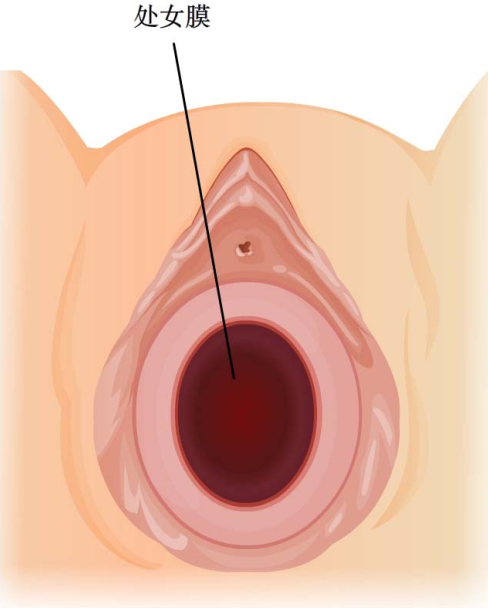

绝大多数患者至青春期发生周期性下腹坠痛,进行性加剧。严重者可引起肛门胀痛和尿频等症状。检查可见处女膜膨出,表面呈紫蓝色;肛诊可扣及盆腔囊性包块。偶有幼女因大量黏液潴留在阴道内,导致处女膜向外凸出、下腹坠痛而就诊。盆腔超声检查可见阴道内有积液。确诊后应及时手术治疗。先用粗针穿刺处女膜中部膨隆部,抽出陈日积血后再进行“X”形切开,排出积血;常规检查宫颈是否正常,切除多余的处女膜,修剪处女膜,再用可吸收缝线缝合切口边缘。

图22-2 处女膜向外膨隆